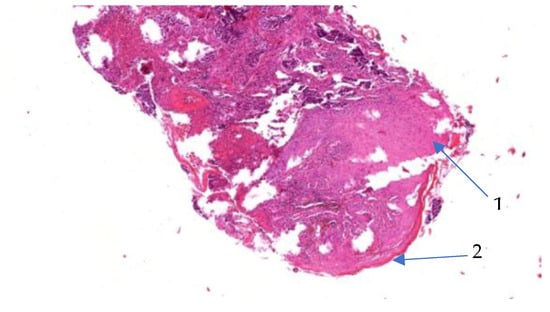

3.2. Case of a 60-Year-Old Male Patient

- Case 2-AI—Suggested AI Future Development